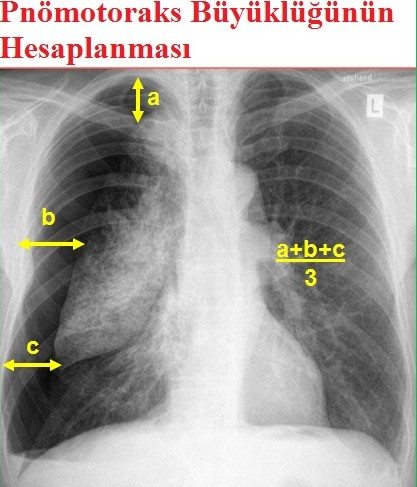

PA akciğer grafisi (ayakta): visseral plevra sınırı görülür. PA normal ama şüphe varsa lateral veya lateral dekubit grafiler çekilebilir. Ekspirium grafisi çok az katkı sağlar. Mediastinal şift; gençlerde minimal pnömotoraksta bile olabilir.

Küçük; viseral-paryetal plevra arası < 2 cm. Büyük; viseral-paryetal plevra arası > 2 cm.